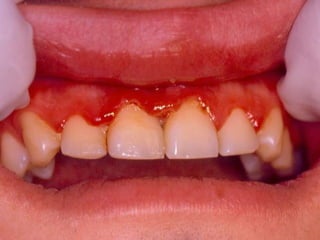

25 - L.C.S., sexo masculino, 18 anos de idade, se apresentou com queixa de aumento de volume na gengiva entre os dentes 23 e 24. Pelo exame clínico, constatamos a presença de um nódulo séssil, de contornos irregulares, coloração avermelhada, com sangramento abundante ao mínimo toque e evolução de 1 ano. O paciente apresentava higiene bucal precária com presença de placa bacteriana e tártaro. Com base no quadro clínico, o diagnóstico é: a) Fibroma e granuloma piogênico. b) Granuloma piogênico e hiperplasia fibrosa inflamatória. c) Lesão periférica (granuloma) de células gigantes e fibroma. d) Granuloma piogênico e lesão periférica (granuloma) de células gigantes. e) Hiperplasia fibrosa inflamatória e fibroma.

Granuloma Piogênico LesãoNodular Séssil ou pediculada Avermelhada ou vinhosa Sangramento espontâneo e áreas de micro-ulceração superficial

Granuloma Piogênico Lesõesnodulares de coloração avermelhada ou vinhosa Provavelmente uma reação inflamatória exagerada ao trauma menor Crescimento rápido, às vezes sangramento espontâneo Ocorre em qualquer idade mas parece mais freqüente em adultos jovens e adolescentes Localização mais comum: gengiva (NEVILLE,2001)

Granuloma Piogênico Lesõesmais antigas, são menos vasculares e mais fibrosas Papila interdental e regiões anteriores são áreas preferenciais, principalmente por vestibular (BORK,1996)